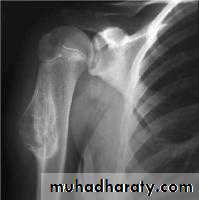

Benign bone tumoursFibrous cortical defect

= non-ossifying fibromaVery common

ChildAccidentally on XR

Pain or pathologic fractureNo malignant potential

Rx : curettage + bone graftOsteoid osteoma